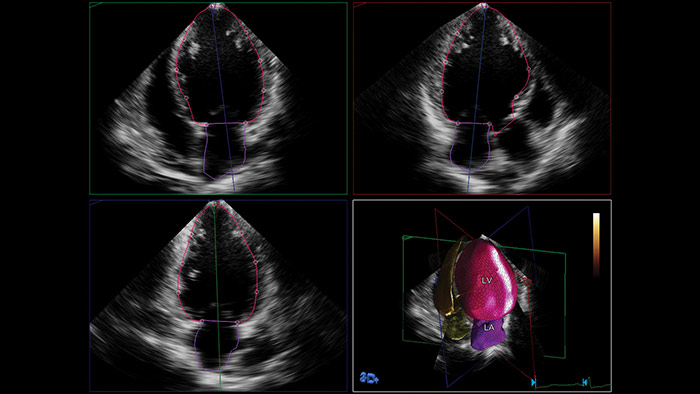

Anatomical Intelligence for Ultrasound (AIUS) di Philips, una tecnologia progettata per potenziare il sistema ecografico. Funzionalità avanzate di modellazione degli organi, sezionamento delle immagini e quantificazione convalidata per agevolare l'esecuzione degli esami e favorirne la riproducibilità, che offrono nel contempo nuovi livelli di informazioni cliniche per rispondere alle sfide economiche e cliniche poste dagli ambienti sanitari odierni.

Le funzionalità AIUS spaziano dall'automazione di passaggi ripetitivi fino all'analisi computerizzata completa di dati non elaborati, con una minima interazione da parte dell'operatore. AIUS è in grado di fornire una documentazione di screening avanzata e misurazioni assistite, oltre al rilevamento di organi e strutture per la registrazione automatica e la quantificazione avanzata.